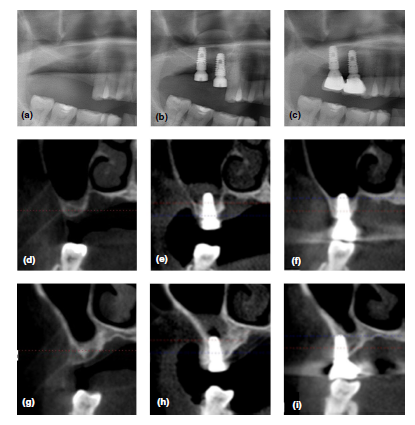

Methods: Dental implants were placed after hydraulic transcrestal sinus lifting and

the filling of saline (20 patients) or PRF (20 patients). Outcome measurements were

implant survival, any complications, and RABH changes. Cone-beam computed tomography

(CBCT) scans were taken and compared preoperatively (T0), immediately

postoperatively (T1), at 3 months (T2), 6 months (T3), and 12 months postoperatively

(T4), respectively.

Results: In a total of 40 patients, 45 implants with a mean length of 10.4 ± 0.8 mm

were placed in posterior maxilla of a mean RABH of 6.8 ± 1.1 mm. The increase in

RABH peaked at T1, and continuous drooping of the sinus membrane was observed

but stabilized at T3. Meanwhile, the gradual increase in the radiopacities was found

below the lifted sinus membrane. The PRF filling induced the radiographic intrasinus

bone gain of 2.6 ± 1.1 mm, which was significantly more than 1.7 ± 1.0 mm of saline

filling at T4 (p < .05). All the implants were in function with no significant complications

over the one-year follow-up period.